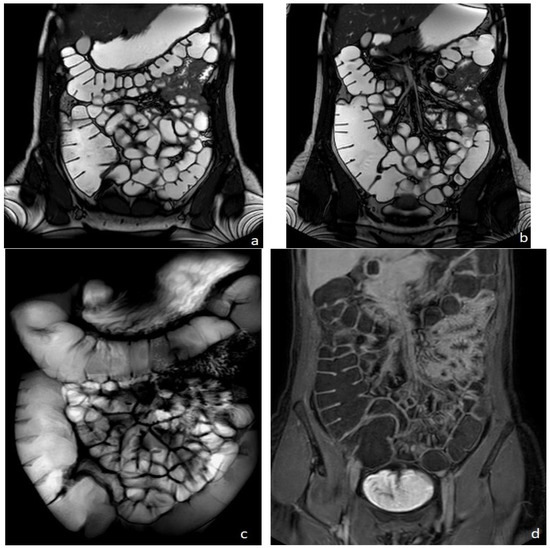

Figure 1.

Healthy woman. MR Enterography. (a,b) are T2 balanced coronal images. (c) is a T2-weighted fat-suppressed single shot coronal image and (d) is a coronal T1-weighted image after intravenousgadolinium-chelate injection.